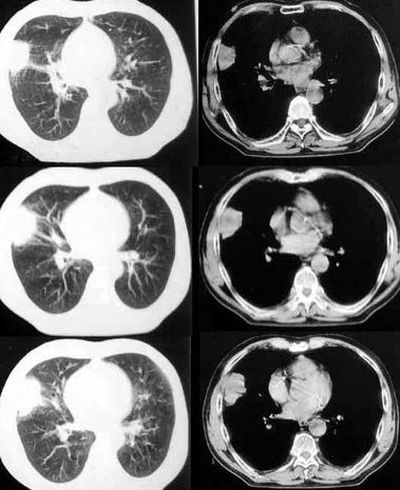

感想:收集了一些本站以孤立结节为主的炎症,结核,肺癌的资料。说实话,即使现在把这些不典型结节混合到一块,不敢保证诊断全部正确,能够以后少犯错就感到达到目的了。其中有那些共性和特异性,有什么需要注意和借鉴的地方,想请大家点评,总结。

肺癌--腺癌

ct1746 pingfanjun提供 结果右上肺腺癌

76岁;咳嗽、咯血、气短、呼吸困难一年余

http://www.radida.com/radinet/read.php?tid=5255

ct1847 九目段提供

m/71y,咳嗽咳痰,痰中带血,低热。

http://www.radida.com/radinet/read.php?tid=7356

ct1962:mzjctmr提供 肺穿病理结果为腺癌

女性,43岁,刺激性干咳4个月,血象血沉正常,无发热

http://www.radida.com/radinet/read.php?tid=7602

ct2060 liuzhiguang 提供 病理中分化型腺癌

http://www.radida.com/radinet/read.php?tid=8557

ct2240 mzjctmr提供 病理结果为高分化腺癌并支气管淋巴转移

女性,60岁,夜间发热一周余就诊。体温38度,血沉35mm/h

http://www.radida.com/radinet/read.php?tid=8574